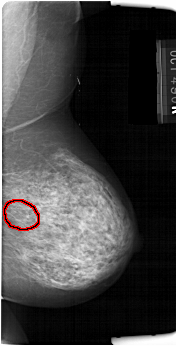

FILE: A_1384_1.RIGHT_MLO.OVERLAY

TOTAL_ABNORMALITIES 1

ABNORMALITY 1

LESION_TYPE CALCIFICATION TYPE PLEOMORPHIC DISTRIBUTION SEGMENTAL

ASSESSMENT 4

SUBTLETY 4

PATHOLOGY BENIGN

TOTAL_OUTLINES 1

BOUNDARY